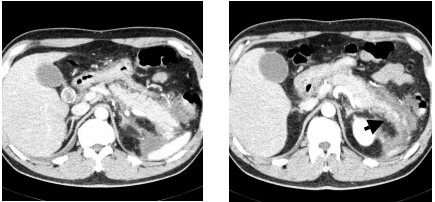

73 一位 20 歲女性,主訴胸痛和咳嗽,胸部影像如附圖,則最可能的診斷為下列何者?

(A)右肺上葉肺炎 (B)右肺中葉肺炎 (C)前縱膈腔腫瘤 (D)右肋膜局限性積液

74 一位 53 歲女性,因左乳癌接受化療,主訴衰弱及呼吸急促,注射對比劑後 CT 影像如附圖,則最可 能的診斷為下列何者?

(A)肥厚性心肌病變 (B)心包膜積液 (C)擴張性心肌病變 (D)縱膈腔淋巴結轉移